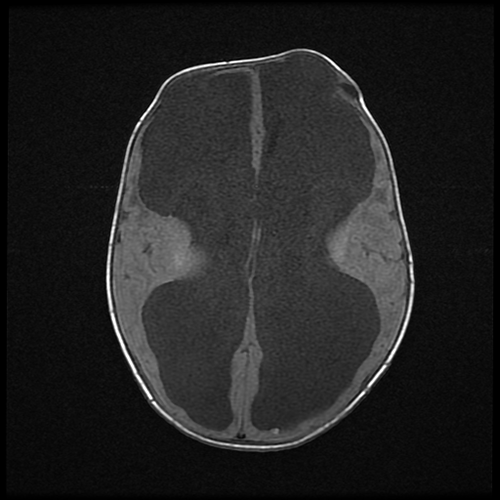

水頭症の単純MRI- 水頭症

水頭症は状況を適正に判断して手術を行います。手術の後に症状が改善しても、数年 (場合によっては数十年)経って急に具合が悪くなることもあるので、定期的に経過をみていく必要があります。